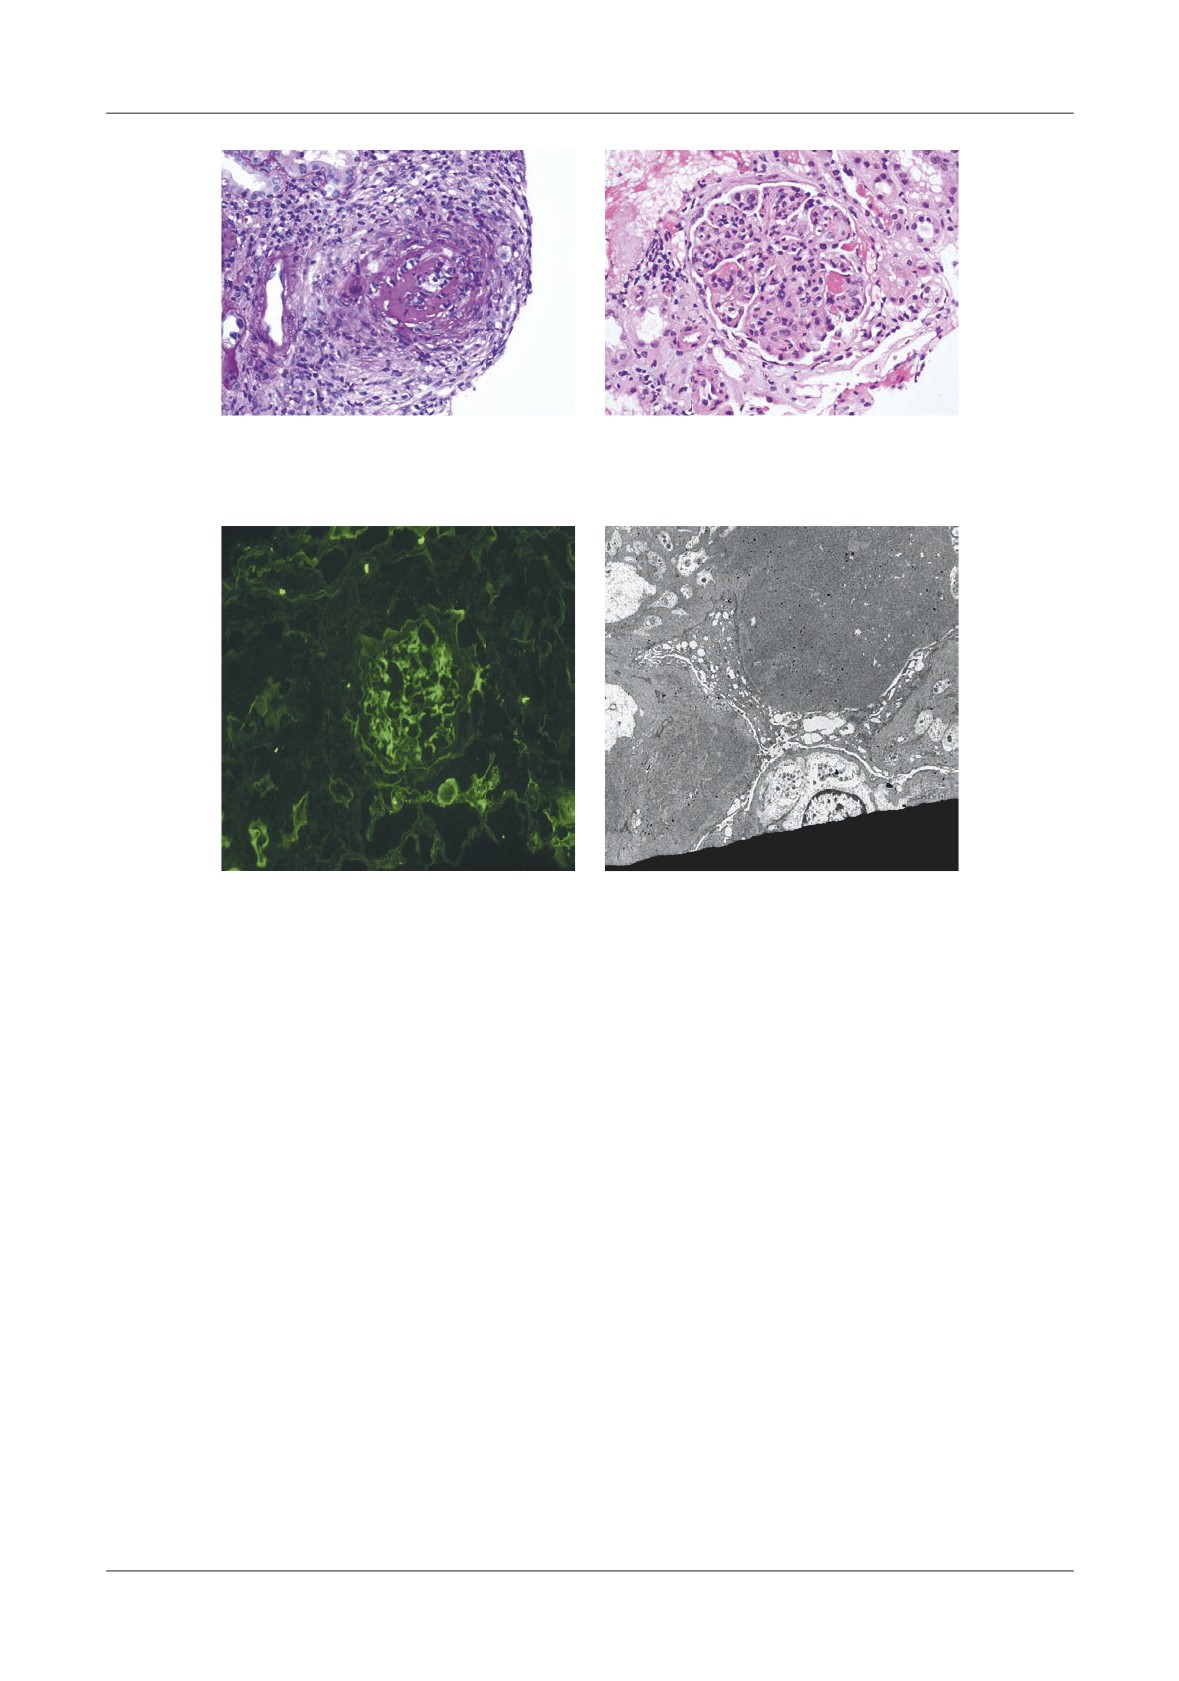

Figures 1,4,5.

and high mortality rates are expected in patients with

Surgical or percutaneous drainage is reserved for

calcium levels <7mg/dL.

cysts  larger  than

5cm  older  than

6  weeks  and

Detection   of   the   mentioned   early   systemic

symptomatic,  pain,  abdominal  mass,  gastric  outlet

complications (Table II) has led to speci c treatment

obstruction, infection or hemorrhage [46].   e presence

options.

of hemorrhagic pseudocyst was 18% in our series of 103

e most frequent indication for intervention in

cysts. In other reports pseudocysts developed in 2% to

severe acute pancreatitis is infected pancreatic necrosis,

31% [37,43,47,48].

and this is a risk factor for abdominal compartment

Proteolytic action of the extravasated pancreatic

syndrome due to visceral and retroperitoneal edema

secretions can explain the gastrointestinal and biliary

[26,27,28] Failure of no operative management mandates

complications in acute pancreatitis, and most of the

abdominal decompression.   is complication is associated

abnormality involving the stomach, duodenum, and

with a very high rate of MSOF and death [29,30,31].

transverse colon, Figure 1, suggested by Aly et al. study

Pancreatic necrosis occurs later in the evolution,

in 2002 [49].

most commonly in the third to fourth week of the

Vascular  complications  in  evolution  of  acute

disease [32,33].

pancreatitis are infrequent; they can result in high

In our study, patients with infected necrosis, the

mortality rates if not detected early, with evolution to

infection was detected within the  rst 2 weeks of illness

pseudo aneurysm and massive hemorrhage [50,51].

24

Sârbu et al

MEDICAL CONNECTIONS • NUMBER 1 (33) • MARCH 2014

ORIGINAL ARTICLES

Most of the major hemorrhagic complications are

11.

Liu TH, Kwong KL, Tamm EP, Gill BS, Brown SD,

secondary  to  a  bleeding  pseudo  aneurysm,  with  a

Mercer DW. Acute pancreatitis in intensive care unit

reported incidence as high as 10% [52]. Intraabdominal

patients: value of clinical and radiologic prognosticators

hemorrhage can be identi ed early by CT imaging [41].

at predicting clinical course and outcome. Crit Care

e incidence of transitory ascites is a relatively

Med 2003;31(4):1026-30.

frequent CT   nding but true pancreatic ascites rarely

12.

Buter A, Imrie CW, Carter CR, Evans S, McKay CJ.

occurs [53].

Dynamic nature of early organ dysfunction determines

outcome in acute pancreatitis. Br J Surg 2002;89(3):298-

Conclusions

302.

13.

Johnson CD, Abu-Hilal M. Persistent organ failure

Mortality  in  acute  pancreatitis  dependents  on

during the   rst week as a marker of fatal outcome in

potentially lethal complications and that can coexist and

acute pancreatitis. Gut 2004;53(9):1340-4.

occur any time in evolution of pancreatitis.    ey can be

14.

Brown A, Orav J, Banks PA. Hemoconcentration is an

divided   into:   early   complications   that   manifest

early   marker   for   organ   failure   and   necrotizing

themselves  within  the   rst

2-3  days;  intermediate

pancreatitis. Pancreas 2000;20(4):367-72.

complications during the second to   fth week; late

15.

Papachristou   GI,  Whitcomb   DC.   In ammatory

complications, that occur within months or years after

markers of disease severity in acute pancreatitis. Clin

the resolution of an acute episode.

Lab Med 2005;25(1):17-37.

e early detection by clinical imaging methods